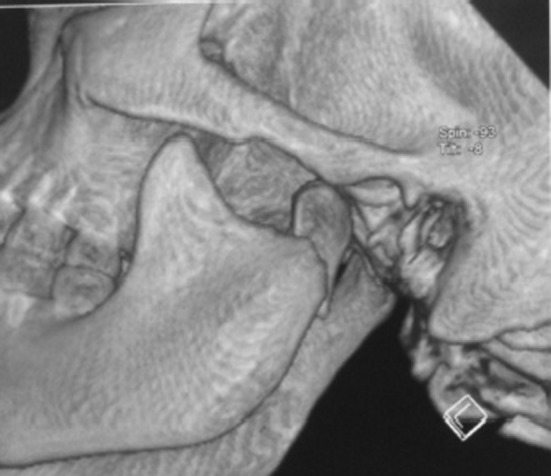

Fig. 2.

3D CT showing medially displaced left condylar fracture

Patients were operated under general anesthesia via preauricular and retromandibular approaches. Patients with fractured dislocation and displacement of mandible condyle in medial direction were managed by preauricular approach. Patients with lateral displacement of mandibular condyle were managed by retromandibular approach. Reverse towne’s and C.T. scan (Figss. 2 and 7) were taken in all the cases prior to surgery to assess the pattern of displacement. Titanium mini plate system was used in all cases for fixation of condylar fracture (Fig. 3).